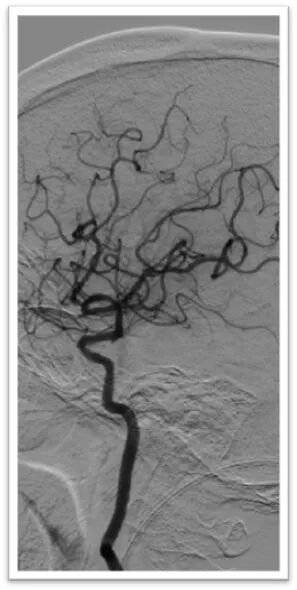

微导丝引导微导管顺利置于左侧大脑中动脉上干,半释放6-30mm支架,停留5分钟后完全取出血栓,造影显示左侧大脑中动脉血流完全恢复,mTICI:3级。

术后即刻造影结果